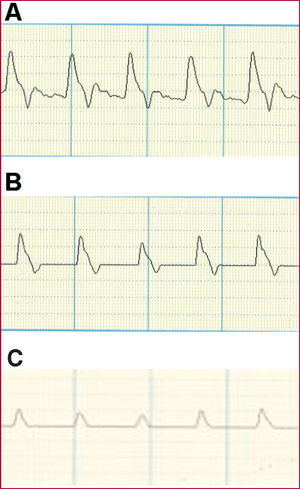

Por último, el registro de la onda velocimétrica obtenida mediante Doppler también puede ofrecer información muy útil mediante la valoración de las modificaciones en los diferentes componentes de la onda velocimétrica arterial (fig. 2).

Fig. 2. Onda velocimétrica Doppler. A: estudio normal. Onda sistólica prominente con dicrotismo en la onda de descenso. B: estudio levemente patológico. Ausencia o disminución del dicrotismo en la onda de descenso. C: estudio muy patológico. Aplanamiento de la onda sistólica.